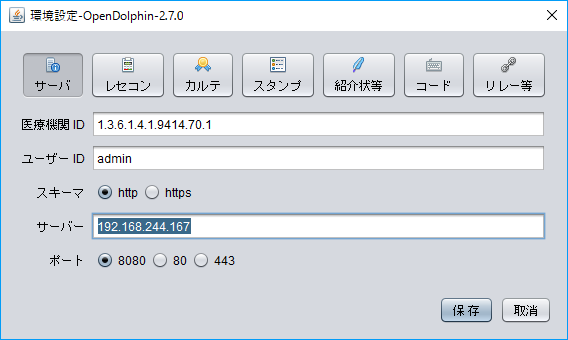

以前ブログで、OpenDolphin(電子カルテ)とORCA(日医レセコン)の環境構築について書いたところ、OpenDolphinデータベースを二次利用できるのかコメントをいただきました。

実際OpenDolphinで電子カルテを運用されている方の参考にもなるかもしれないので、仮想マシンでの環境構築とRstudioでの接続までを書いておきます。

インストール用のスクリプトは上記ブログ内のものとほぼ同じですが、OpenDolphinのDockerコンテナで使用しているPostgreSQLと、ORCAのPostgreSQLのポートがぶつからないように、Docker runするときにPort(5433)を指定しています(通常は5432)。RstudioもクライアントPCにインストールするのが面倒なので、Dockerコンテナで入れちゃいます。

では今回のポイントのOpenDolphinとRstudioの接続です。

Rstudio serverはDockerコンテナで動いているので、仮想マシン(Ubuntu)のIPアドレスとポートをクライアントPCのブラウザーに入力します。

例)192.168.244.211:8787

UsernameとPasswordは共にrstudioです。

これでRstudio severに接続できます。

OpenDolphinとORCAの簡単な環境構築

OpenDolphinは日医レセコンORCAに接続できる、オープンソースの電子カルテです。

極力インストールの手間を省略するためと、ホストOSの環境をよごさないために、VMwareの仮想マシンにUbuntu64,14.04LTSをインストールし、そこにORCAをインストールします。またOpenDolphinはUbuntuのDockerを利用してインストールします。

Ubuntuが苦手、Dockerがわからなくても環境構築できるように、シェルスクリプトを使ってコード入力を少なくすることにします。

OpenDolphinクライアントのインストール

次のURLからクライアントソフトをダウンロードします。Javaバージョン8の実行環境が必要なので予めインストールしておいてください。

https://i18n.opendolphin.com/dolphin/client/OpenDolphin.zip